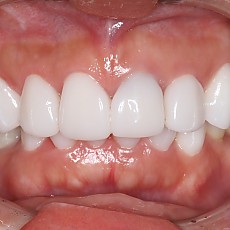

시술전후사진 6 페이지

Total 189건 6 페이지